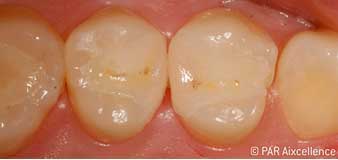

Рис. 1. Начальный вид зубов без клинических признаков кариеса

Рис. 2. Освещение зондом Facelight используется здесь в качестве трансиллюминации для распознавания непрозрачных областей. Соединения порфирина при такой форме освещения не активируются